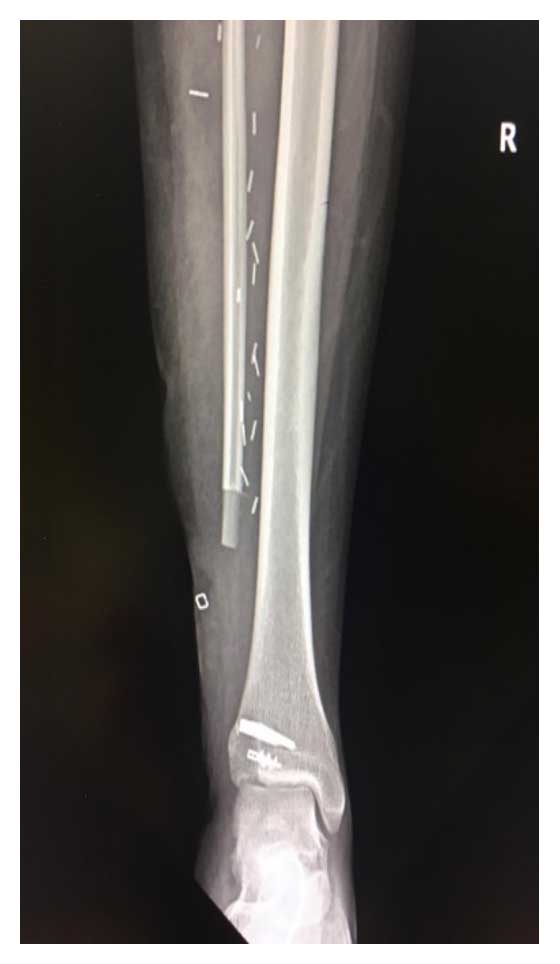

Ameliyat Sonrası: Röntgende distal fibula rezeksiyonu ve anchor ile ligament rekonstrüksiyonu görülmekte.